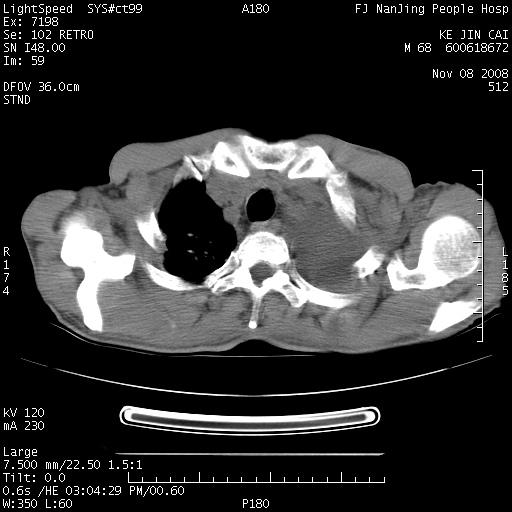

是个很有看头的病例,咋人气那么不旺?没多少人兴趣呢?这个病例几大怪:1   恶性肿瘤侵犯心肌左房怪,心肌一般不会被恶性肿瘤侵犯吧?2   左下肺均匀实变怪,内无含气,有别一般不张实变,含气肺泡完全为液体取代,而非一般不张实变的肺萎陷,冷不丁还以为是肿大的脾脏3   肿瘤本身怪,像tb肺不张4   这么有看头的病例没人气怪。呵呵。

左肺恶性肿瘤侵犯肺动脉,左心房内瘤栓,胸膜转移。

左肺恶性肿瘤侵犯肺动脉,左心房内瘤栓,胸膜转移,少见,学习了。